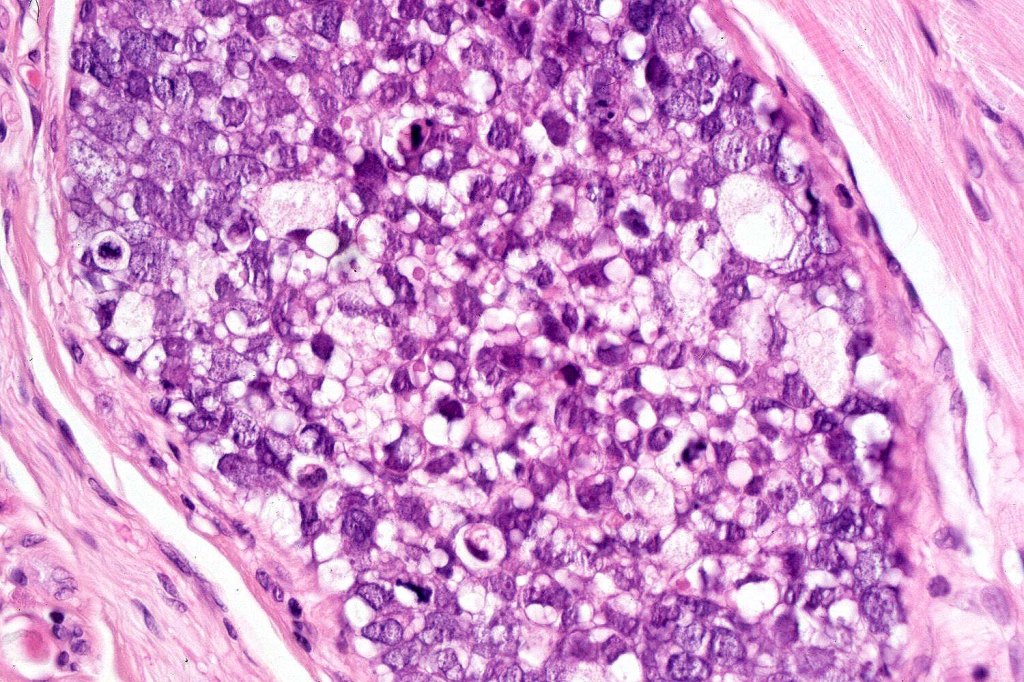

•Tumors are composed of an admixture of darkly staining basaloid cells with hyperchromatic or vesicular nuclei and more obvious sebaceous cells with eosinophilic, bubbly, multivacuolated cytoplasm frequently indenting the nucleus (scalloped)

•Often mitoses are numerous and abnormal forms evident

•Well differentiated examples can be deceptive unless one looks carefully for pleomorphism, necrosis, excessive mitotic activity and abnormal mitoses. Be careful diagnosing sebaceous adenoma, particularly large examples arising in the elderly